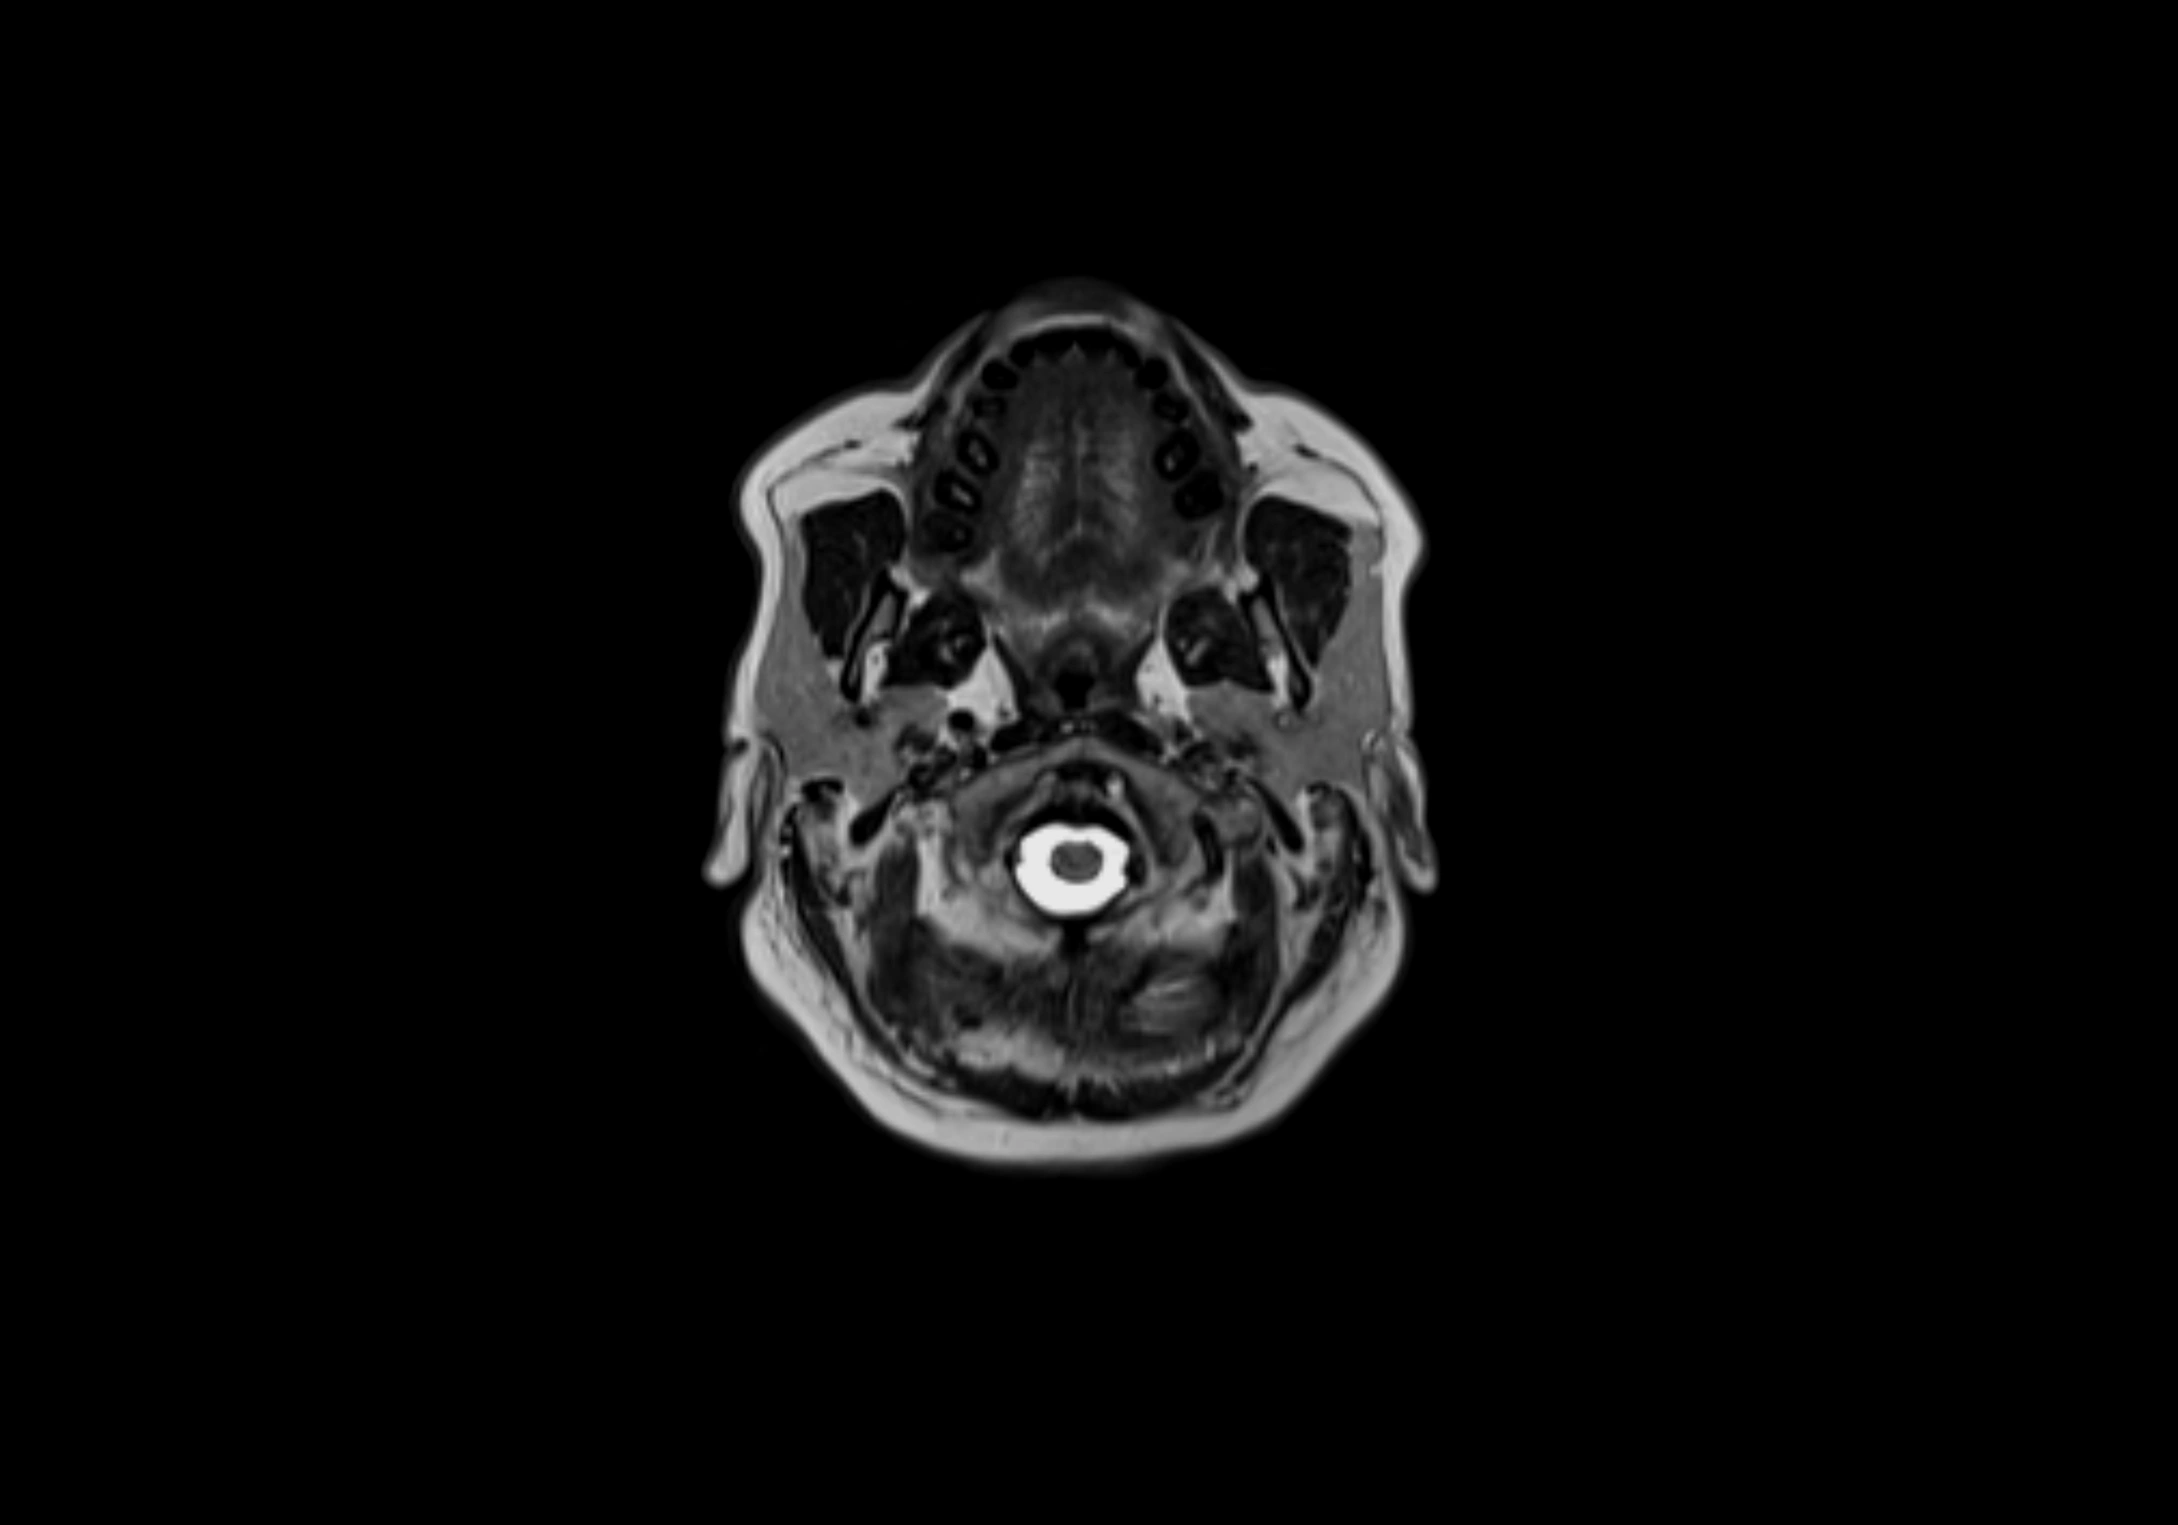

MRI images

image